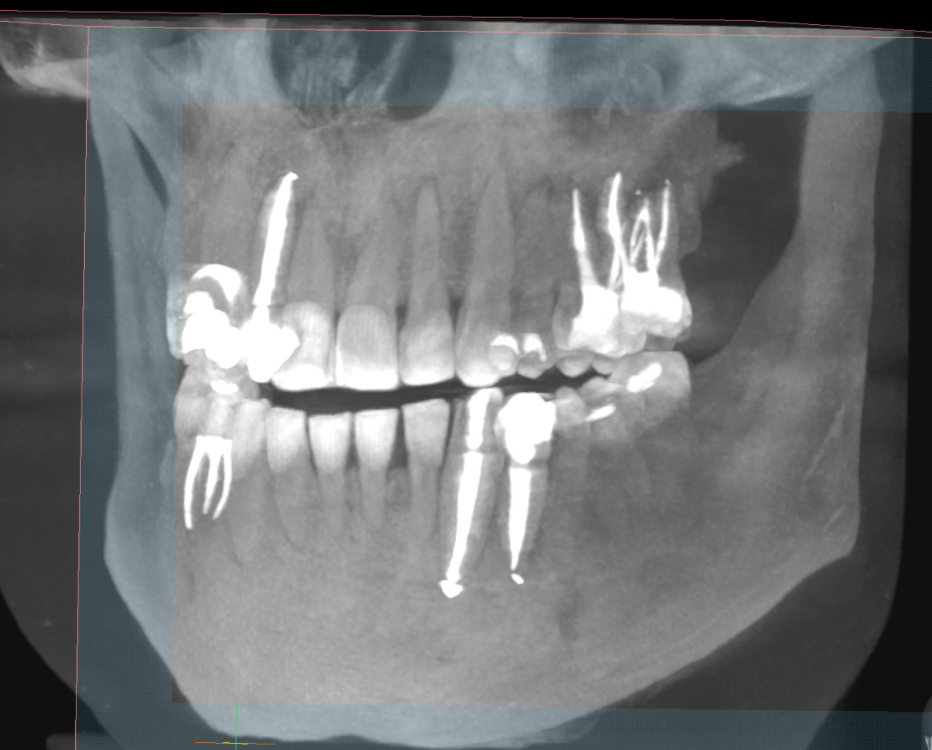

sewif Опубликовано 23 мая, 2021 Автор Поделиться Опубликовано 23 мая, 2021 Здравствуйте Сегодня сделал снимок. Прошу почти год с предыдущего снимка. В этот раз делал снимок как сказал доктор - в Пикассо. Программа непонятная и может скриншоты не очень, если нужно как-то иначе то прошу сообщить. Я не вижу кисты, ее нет или я не так смотрел? Ссылка на комментарий

Irouil Опубликовано 23 мая, 2021 Поделиться Опубликовано 23 мая, 2021 Эти картинки не особо показательны, конечно, но очевидно, что от изначальной ситуации тут не осталось примерно ничего 1 Ссылка на комментарий